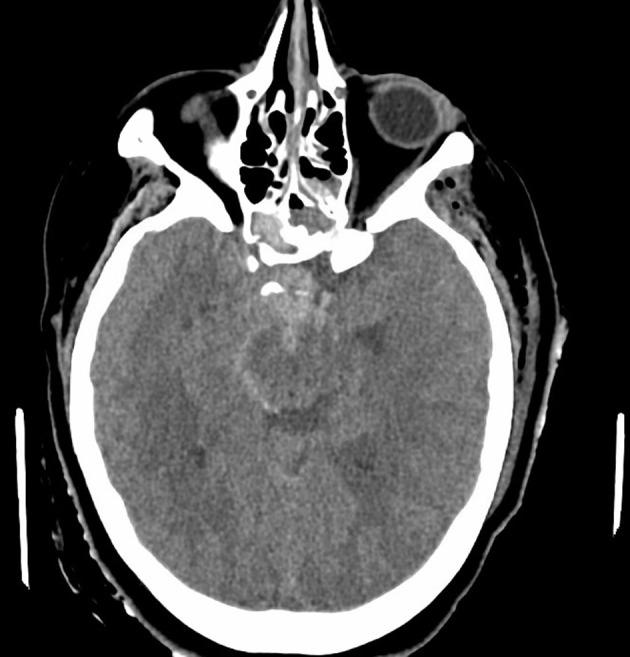

A 24-year-old female with history of traumatic brain injury with associated skull fractures due to a gunshot wound to the head 6 months prior presented to the ED in hemorrhagic shock secondary to epistaxis. After stabilization with the administration of blood products, Computed Tomography with Angiography (CTA) imaging of the head and neck was obtained and revealed a 3.1 × 2.2 × 2.5 cm pseudoaneurysm of the cavernous portion of the right internal carotid artery penetrating through the base of the skull into the ethmoidal sinus. The patient was taken for formal angiography by interventional radiology-and a partially thrombosed daughter sac of the initial aneurysm was identified and believed to be the source of the hemorrhage. The aneurysm was successfully coiled and occluded using ONYX embolization. Postoperatively, the patient returned to her baseline mental status without any acute complaints. The patient was discharged back to her nursing home 2 days later with a 3-week follow-up CTA revealing persistent occlusion of the aneurysm and a patent internal carotid artery.

一名24岁女性,6个月前因头部枪伤导致创伤性脑损伤并伴有颅骨骨折,因鼻出血继发失血性休克被送往急诊科。在输注血液制品使其病情稳定后,对头颈部进行了计算机断层血管造影(CTA)成像检查,结果显示右侧颈内动脉海绵窦段有一个3.1×2.2×2.5厘米的假性动脉瘤,该动脉瘤穿过颅底进入筛窦。患者被介入放射科送去进行正式血管造影,发现了最初动脉瘤的一个部分血栓形成的子囊,并认为这是出血源。使用Onyx栓塞剂成功地对动脉瘤进行了弹簧圈栓塞和封堵。术后,患者恢复到基线精神状态,无任何急性不适主诉。患者于两天后出院回到养老院,3周后的CTA随访显示动脉瘤持续闭塞,颈内动脉通畅。